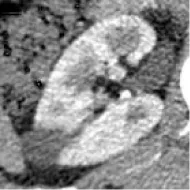

Patients with a pathological diagnosis obtained by biopsy or surgical resection were included in this study. In addition, 80 patients with available arterial/cortical/nephrogenic phase CT image sequences were reviewed (42 with PRCC and 38 with ChRCC). After randomly selecting 6 cases (3 PRCCs and 3 ChRCCs) for testing sets, the images of 74 tumors (39 PRCCs and 35 ChRCCs) were used to build the datasets. The CT images were obtained using various radiology scanners and non-standard protocols. Arterial phase sequences were preferred when multiple phases existed. Whole sequences were retrieved and exported utilizing the hospital radiological database. The window settings were 40 HU (width) and 400 HU (level). Based on the clinical and pathological data, ROIs of sequences were segmented, labeled, and exported with ITK-SNAP by two abdominal radiologists who have experience of more than 10 years in the diagnosis of urinary system tumor. After cross-validation, images that were exported in.jpg size included 857 images of ChRCCs and 997 images of PRCCs. Labeling was applied in the non-graphical layer so that each slice filename contained the case number, gender, age, and histological subtypes. After resizing, images comprised matrices with 256 * 256 pixels in the axial planes. The dataset was divided into the training set and validation set (90% for the training set and 10% for the validation set).